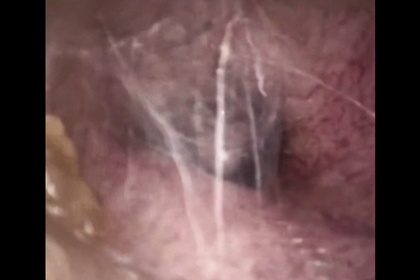

Доктор начал со стандартной процедуры: с помощью эндоскопа исследовал слуховой проход и испытал шок. В ухе китайца сидел паук, окруженный паутиной. Инородный объект удалось быстро удалить.